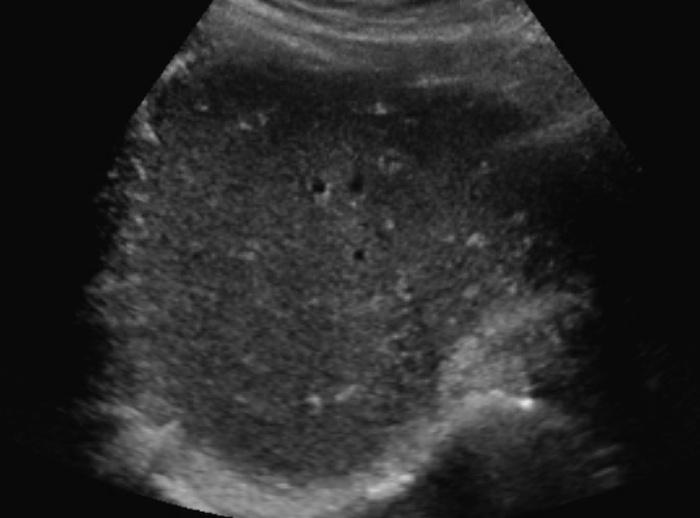

Fatty Liver Infiltration